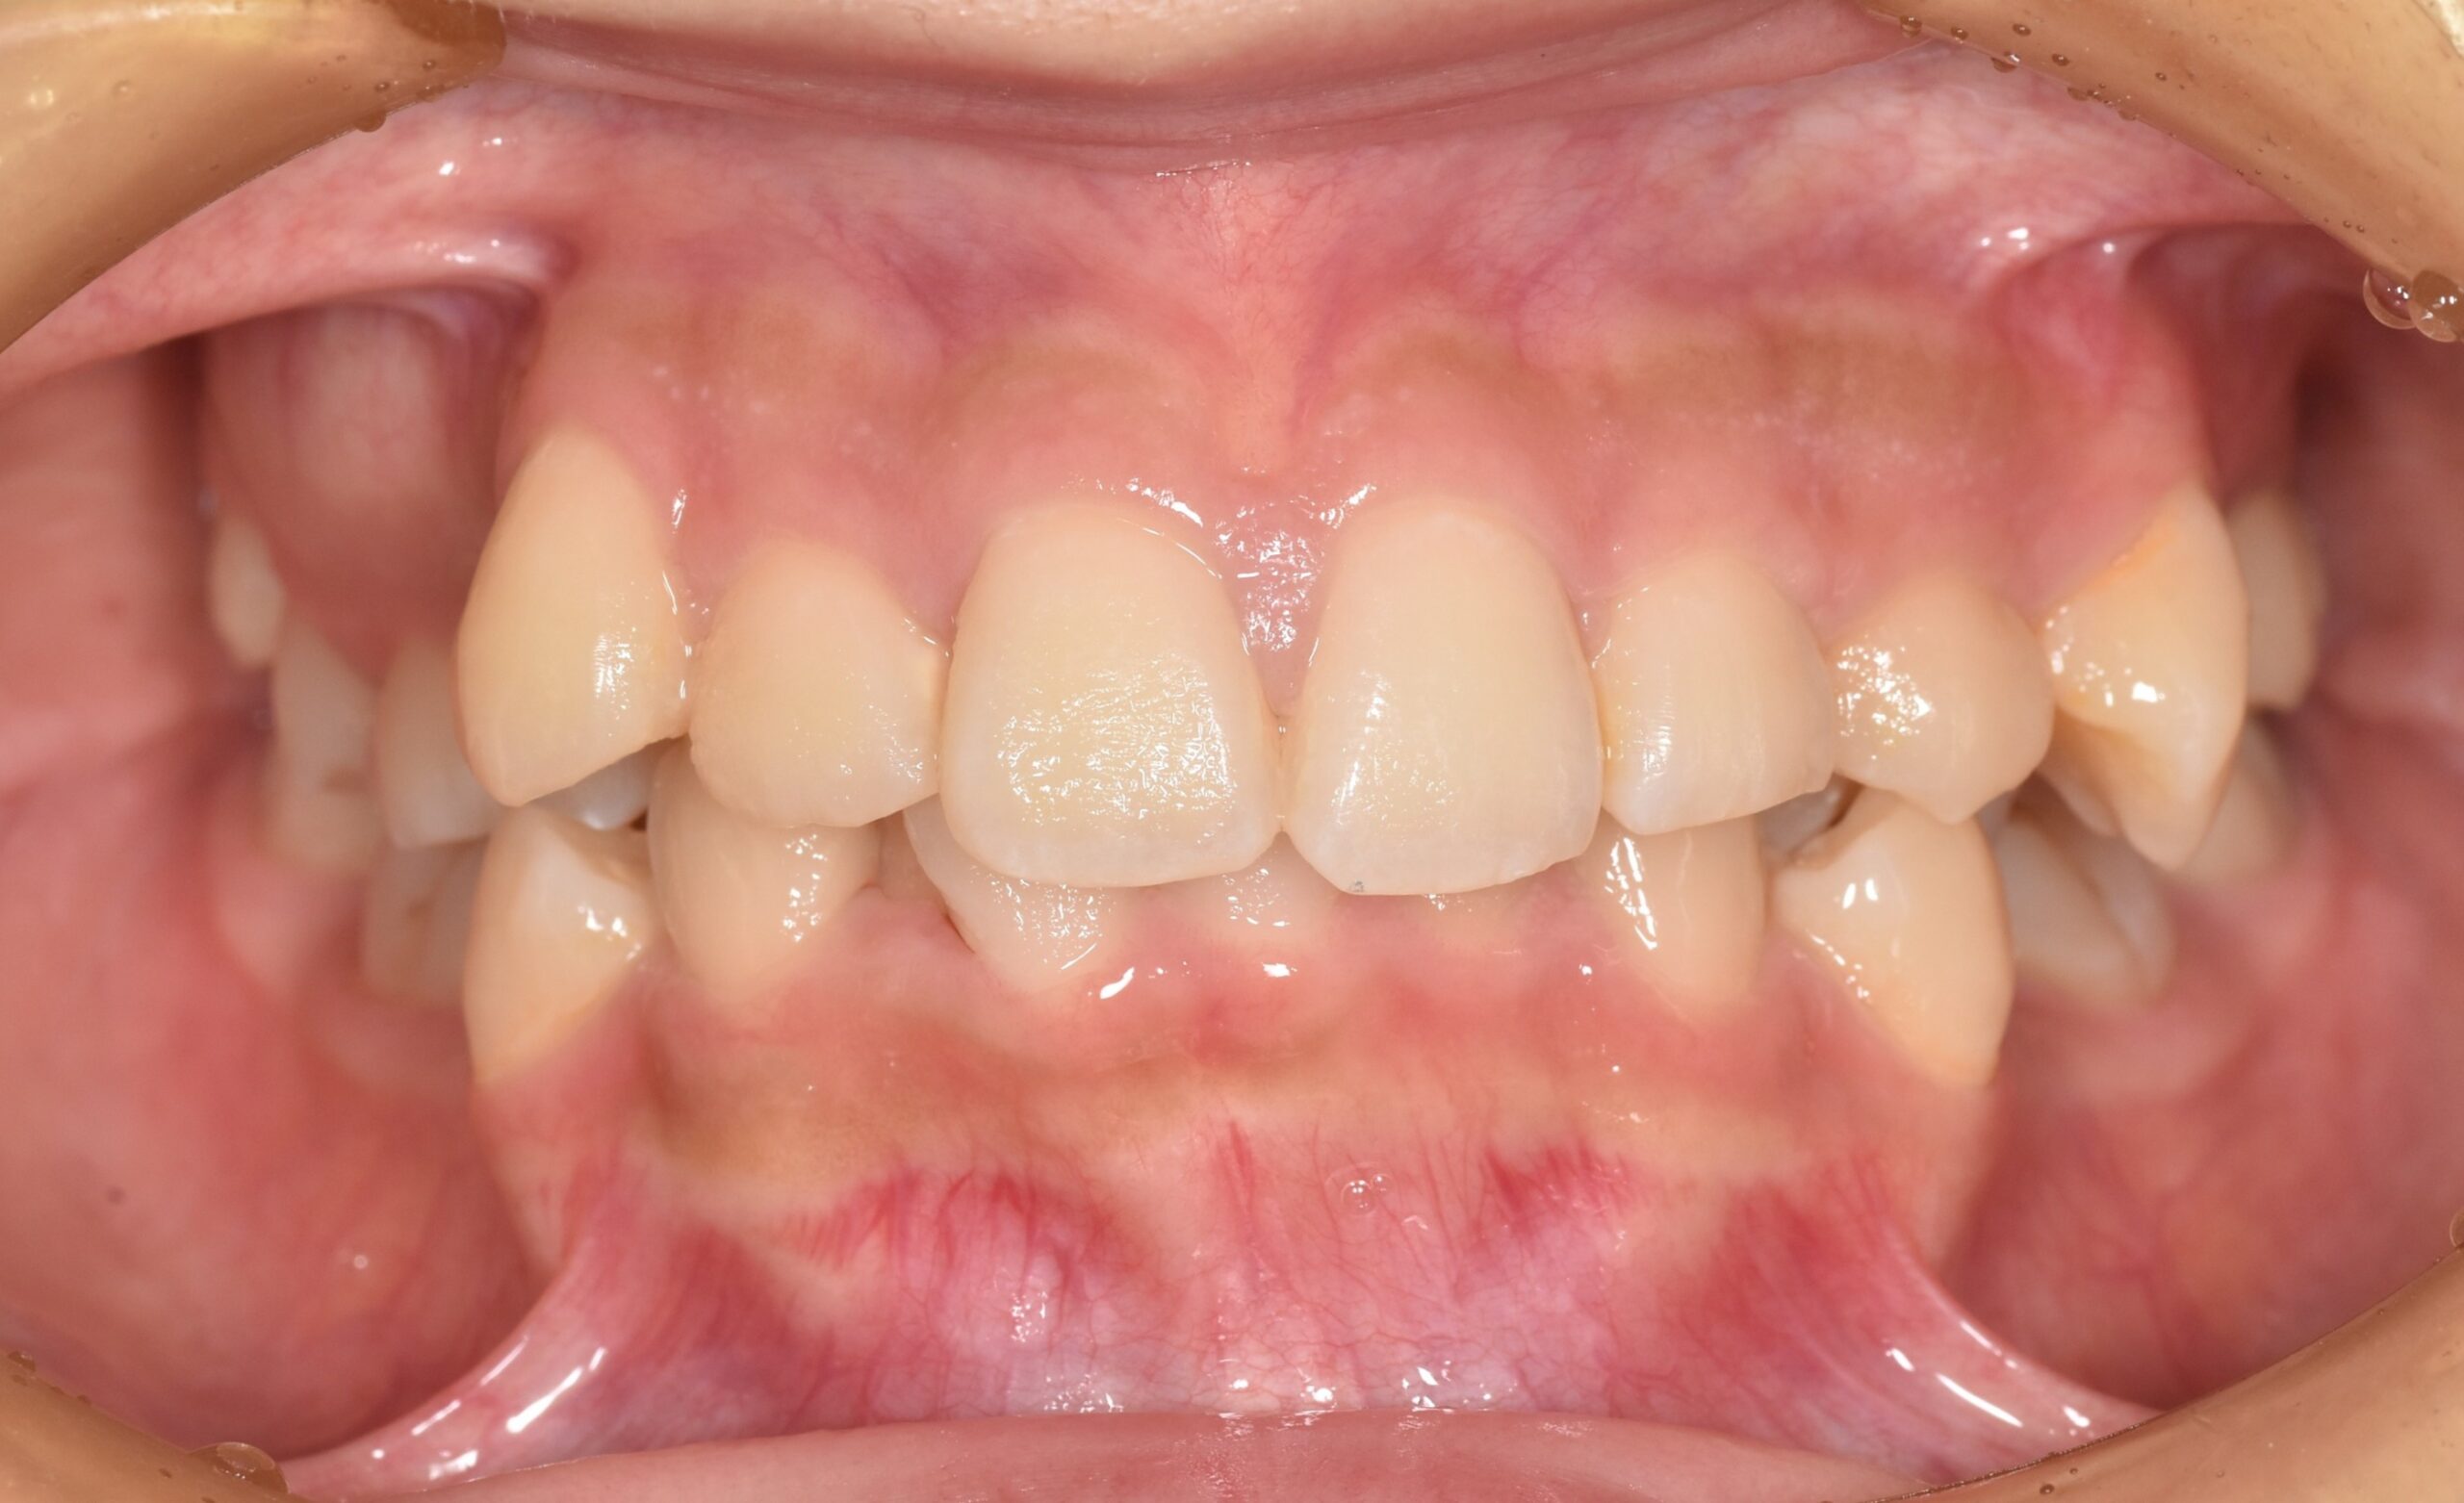

BEFORE

| 年齢 | 19歳 |

|---|---|

| 主訴 | ガタガタが気になる |

| 症状 | 過蓋咬合を伴う叢生症例 |

| 治療内容 | 過蓋咬合を伴う叢生症例と診断し上下顎両側第一小臼歯の抜歯を行い、マルチブラケット装置を用いて治療を行いました。上顎は裏側の矯正装置、下顎は表側の矯正装置で治療を行いました。ハーフリンガル矯正治療。 |

| 抜歯部位 | 上下顎両側第一小臼歯 |

| 治療期間 | 3年 |

| 費用(税込) | 1,045,000(税込)別途処置料 |

| 治療のリスク | 虫歯、歯周病の悪化、歯肉退縮、歯根吸収、顎関節症の悪化、後戻り |